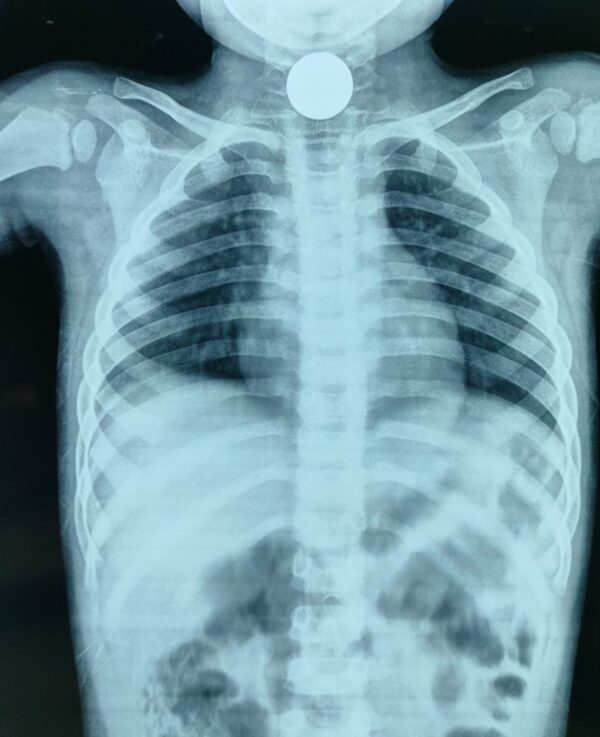

चम्पावत : शनिवार की सुबह चम्पावत के एक परिवार के लिए अचानक घबराहट और बेचैनी से भरी साबित हुई। खेलते-खेलते एक मासूम ने ऐसा कर दिया जिसकी किसी को उम्मीद नहीं थी — बच्चे ने गलती से एक सिक्का निगल लिया। बच्चे की साँसें उखड़ने लगीं, गले में तेज़ दर्द और घबराहट ने पूरे परिवार को झकझोर दिया। माता-पिता घबराए हुए तुरंत उसे लेकर जिला अस्पताल चम्पावत पहुंचे। अस्पताल पहुंचते ही डॉक्टर्स ने बिना समय गंवाए एक्सरे जांच की, और यह साफ़ हो गया कि सिक्का बच्चे के गले में अटक गया है।

बच्चे को तुरंत ऑपरेशन थिएटर ले जाया गया। वहाँ डॉक्टरों की टीम ने दूरबीन तकनीक (एंडोस्कोपी) के माध्यम से बेहद सावधानी से सिक्के को बाहर निकाला। यह आसान नहीं था, लेकिन चिकित्सा टीम की कुशलता और तत्परता ने एक बड़ी अनहोनी टाल दी। कुछ समय बाद जैसे ही बच्चे ने सामान्य रूप से सांस लेना शुरू किया, अस्पताल के कमरे में राहत की हवा भर गई। माता-पिता की आँखों में डर की जगह आँसू और मुस्कान दोनों थे। उन्होंने पूरी चिकित्सक टीम का तहे दिल से आभार जताया।